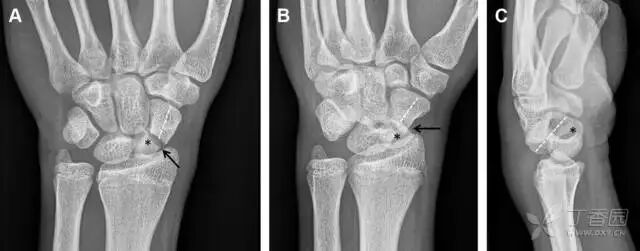

30桡骨远端骨折

常规进行前后位、侧位、斜位 X 线检查,对于大多数桡骨远端骨折来说不容易漏诊;但是对于无移位的骨折,特别是桡骨茎突骨折,容易漏诊。桡骨茎突骨折是一斜行的骨折,常累及关节面,常发生于轴向应力或直接打击。

图 1 57 岁女性,摔倒后手掌撑地,桡骨茎突压痛。(A~C)前后位、斜位、侧位片示软组织肿胀(*)和发丝样骨折(白色箭头);(D~F)2 周后,前后位、斜位、侧位片示骨折线显明,由于新骨痂沉积而呈现透亮线与硬化线并存;(G~I)另一患者,桡骨茎突骨折在前后位及侧位片上显示不明显,而在斜位片显示更清楚